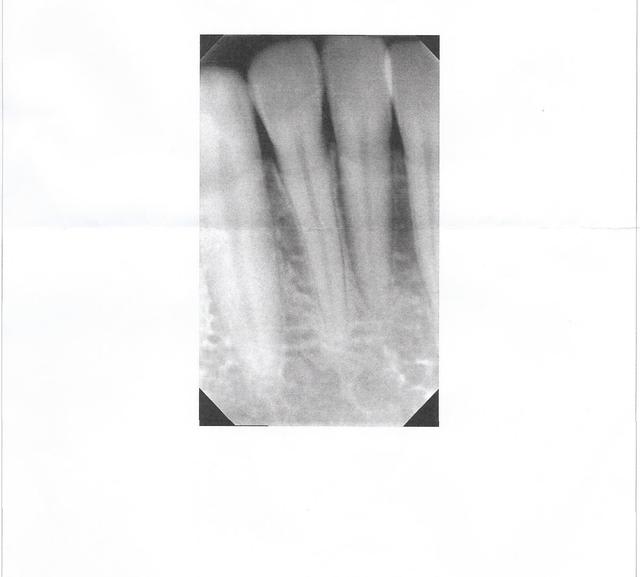

Absolument rien à signaler sur cette radio

> Absolument rien à signaler sur cette radio